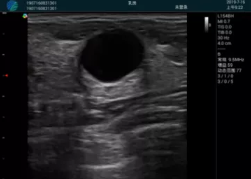

清晰顯示孕囊,通過軟件包計算孕齡7w+6d

M20實時引導,術(shù)中清晰顯示孕囊被破壞和抽吸針的過程,清晰顯示吸引針

抽吸結(jié)束后縱切子宮,孕囊已被完全抽吸,未見明顯殘留

橫切子宮,發(fā)現(xiàn)右側(cè)宮腔靠近宮角處有少許脫模樣殘留

M20引導下,抽吸針找到右側(cè)宮角處再次清掃

二次抽吸后再次進行超聲檢查,宮腔未見殘留,宮腔線清晰顯示